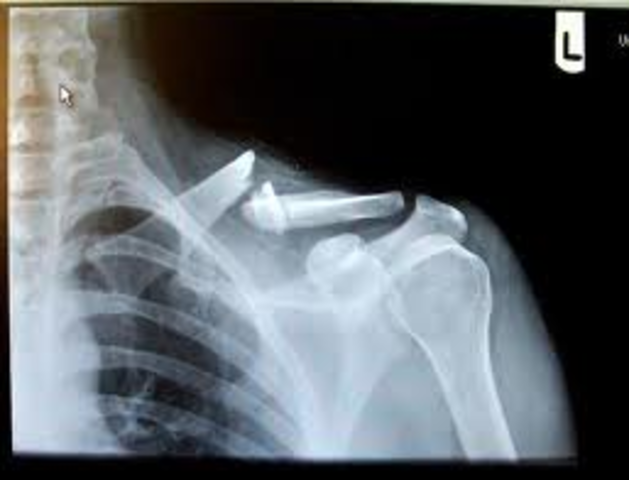

• The Day I Broke My Collar Bone

The Day I Broke My Collar Bone

Okay it wasn't really me who broke it was my brother, Brandon's fault. One day we were just messing around and he jumped on me and it snapped just like that. The ride to the hosptial seemed like it took forever I had to be in a sling for 6weeks.